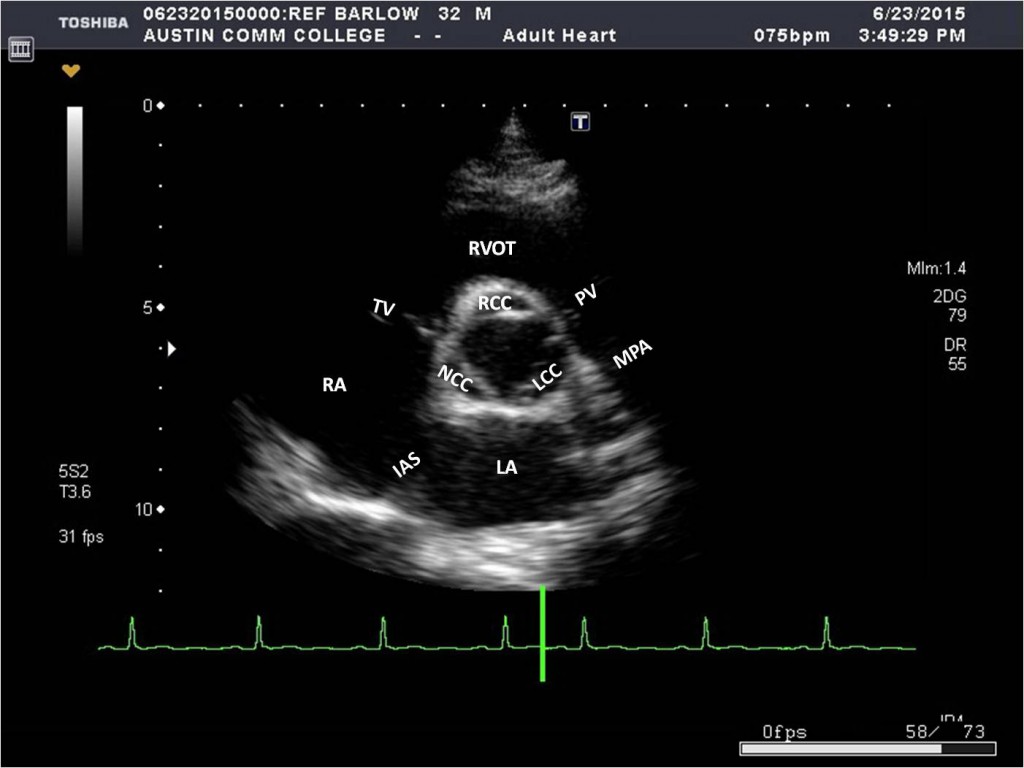

What structures are seen in the SAX level of the aorta/aortic valve? (transducer is angled inferiorly - can also slide inferiorly from the pulmonary bifurcation view)

* RVOT

* PV

* MPA

* AO and Aortic cusps (RCC, LCC, NCC)

* RA

* LA

* IAS (interatrial septum)

* TV (anterior and posterior leaflets)

* Occasionally the left main coronary artery (LMCA)